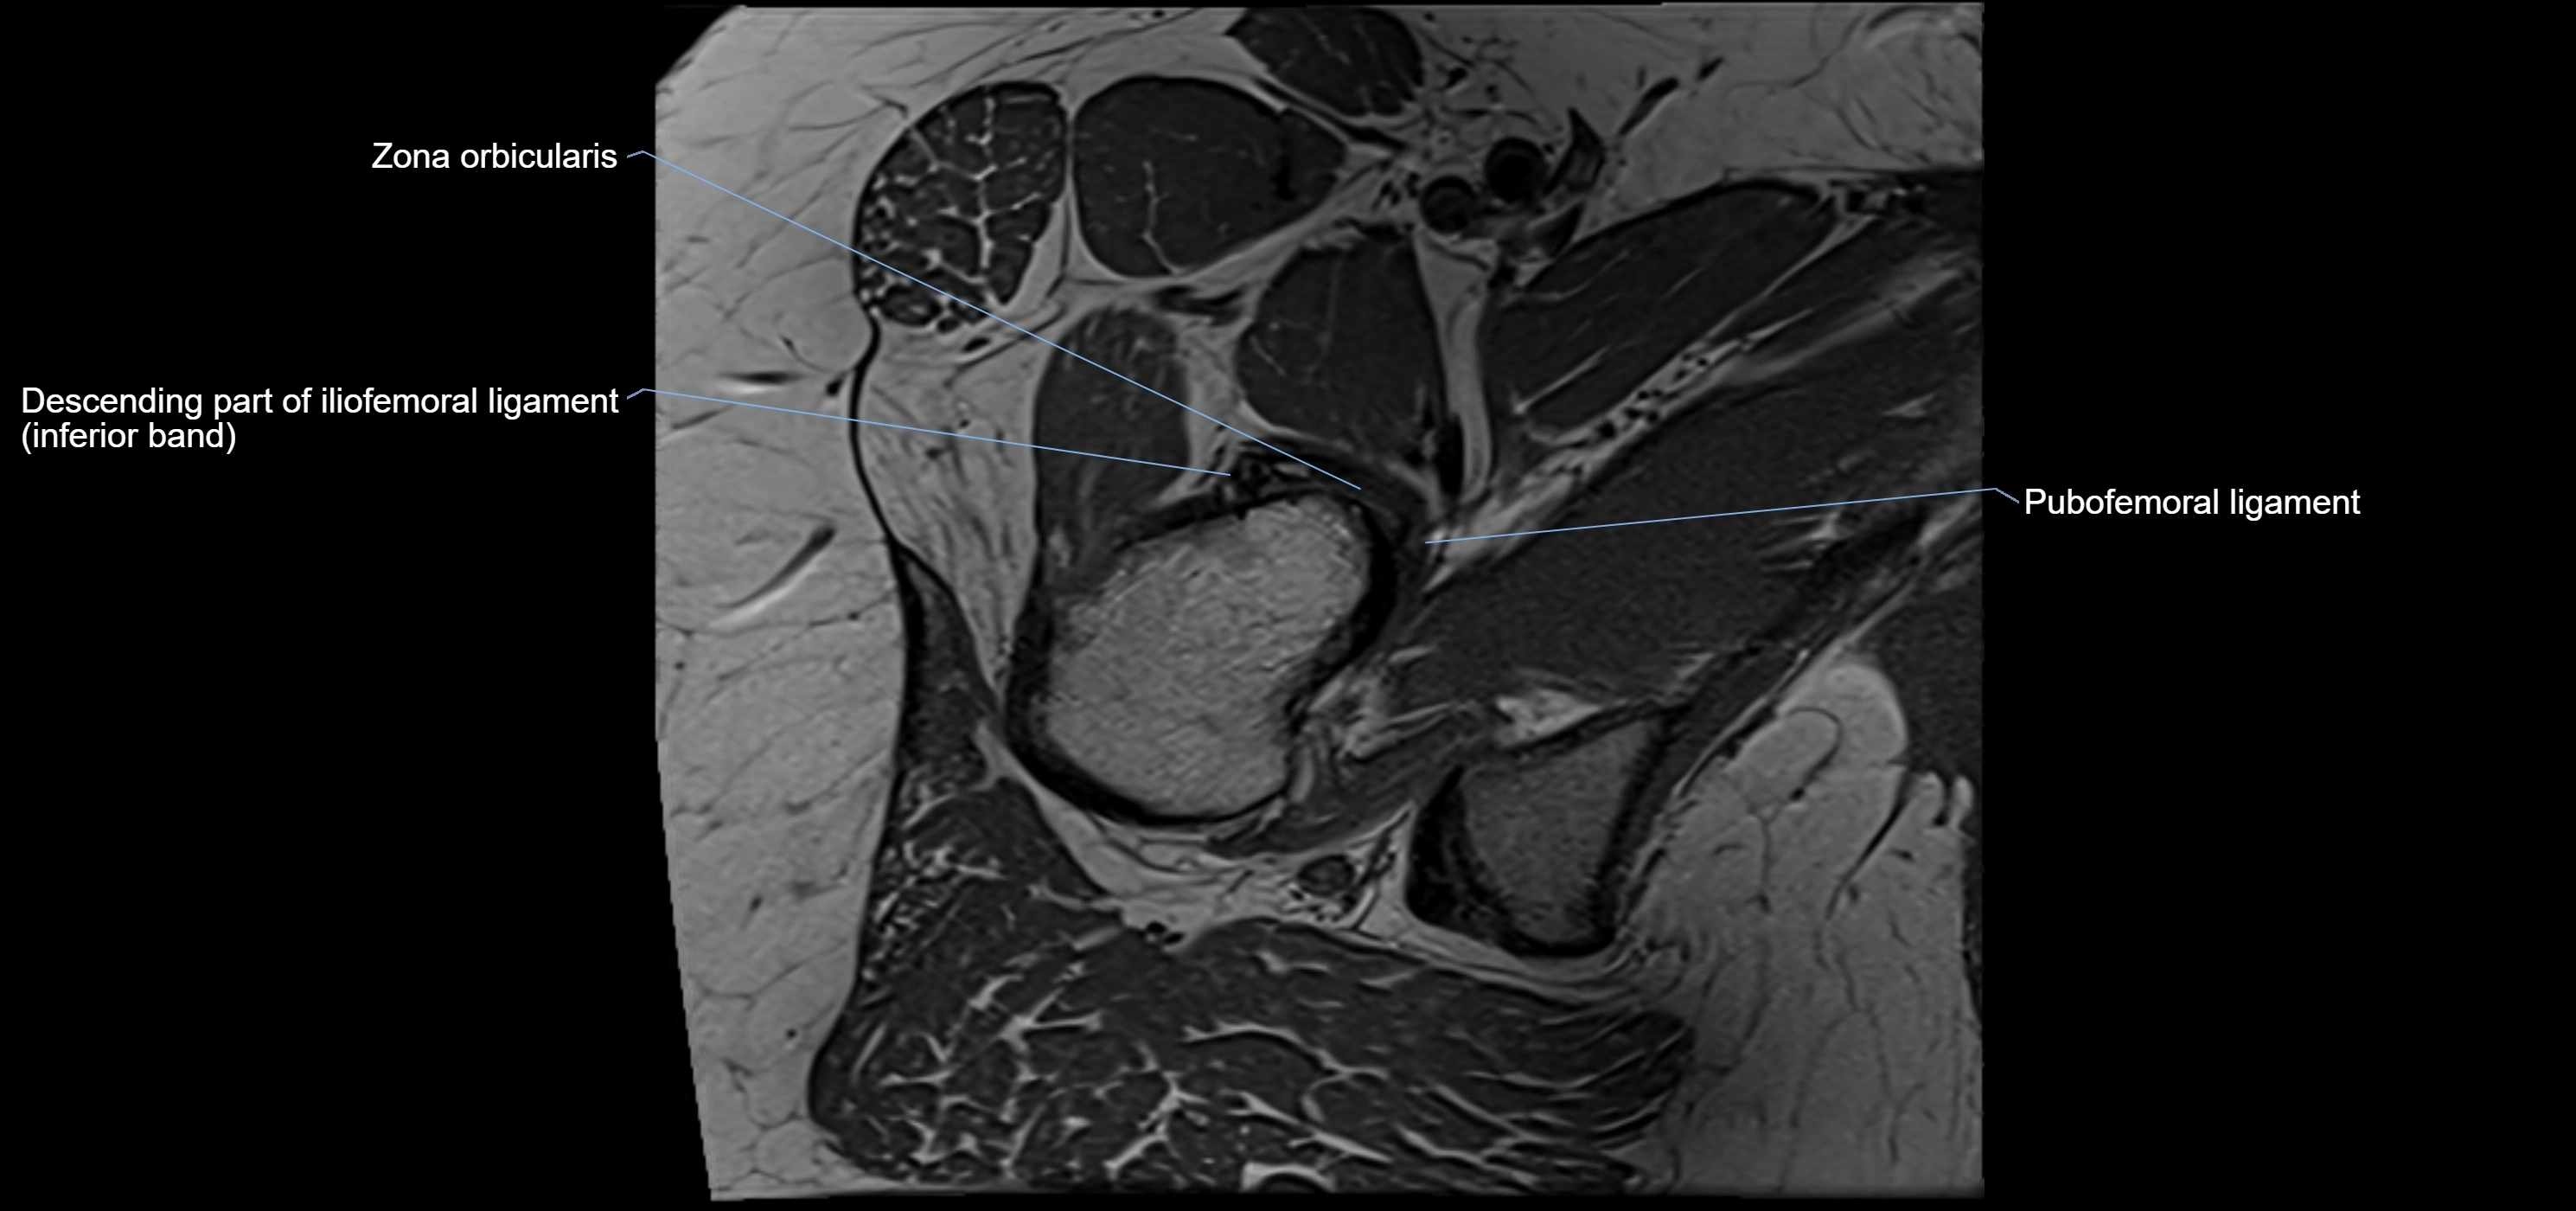

MRI image

image

MRI Appearance

T1-weighted images:

• Labrum: low signal intensity (dark)

T2-weighted images:

• Joint fluid: bright, making labral tears visible as fluid extending into or around labrum